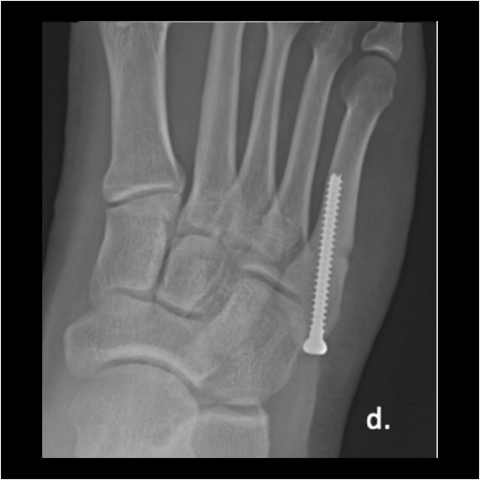

Figure 1d

Figure 1d. We fixed his fracture with an intramedullary, fully-threaded, cannulated 4.5mm screw. He returned to training at 3 months. As shown here, the fracture looked healed at 6 weeks postop.